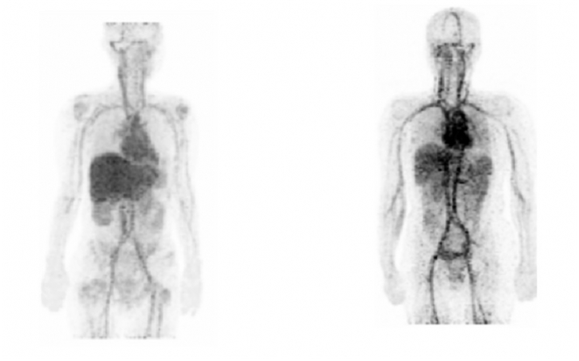

<유방암 환자에게 방사성동위원소 구리-64를 주사해 유방암 발병과 치료효과를 정밀하게 영상으로 확인할 수 있는 기술 개발, 한국원자력의학원, 2017년>